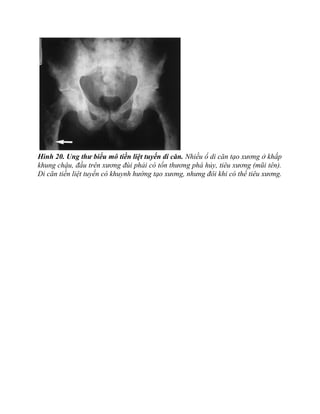

Hình 20. Ung thư biểu mô tiền liệt tuyến di căn. Nhiều ổ di căn tạo xương ở khắp

khung chậu, đầu trên xương đùi phải có tổn thương phá hủy, tiêu xương (mũi tên).

Di căn tiền liệt tuyến có khuynh hướng tạo xương, nhưng đôi khi có thể tiêu xương.